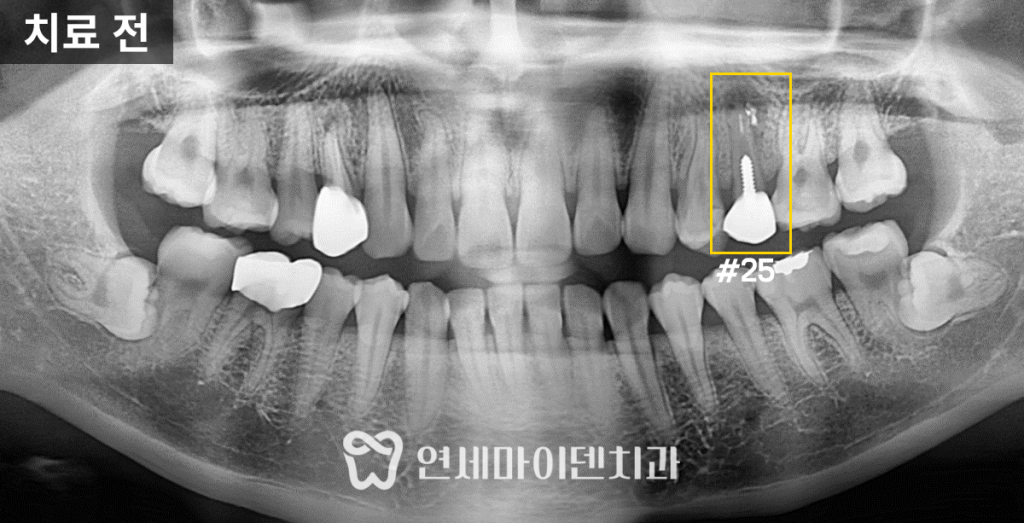

실제로 파노라마 상으로 해당 치아의 주변 뼈가

까맣게 녹은 것을 확인할 수 있습니다.

내원 당시 사진을 살펴보면

고름이 계속 나왔던 잇몸 부위는 흉터처럼 흔적이 남았습니다.

무엇보다 문제의 치아 내부에는 금속 기둥(포스트)가

세워져 있었습니다.